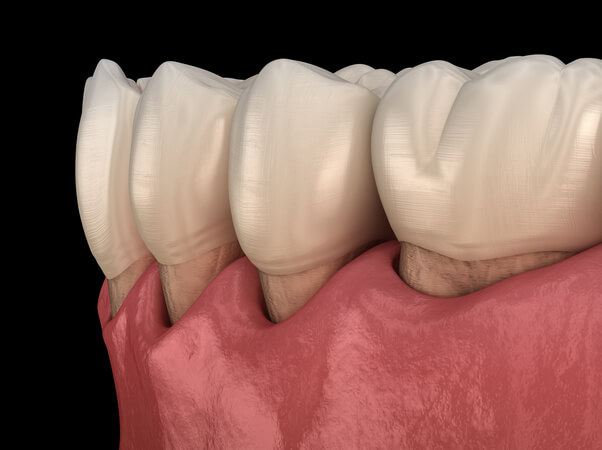

Feeling long in the tooth? A gum graft (also known as a gingival graft or periodontal plastic surgery) is a collective name for a surgical procedure that aims to cover an exposed tooth root surface with grafted gum tissue. Exposed tooth roots are usually the result of gum recession due to periodontal disease. There are other common causes, including overly aggressive brushing and trauma.

Over time, gum recession can continue to the point where the protective type of gum around your teeth is nearly gone, and the roots of your teeth are left open to chronic gum infection and bone loss around that tooth. Decay can also form along the root, which can also cause some bothersome sensitivity in the area.

- Improved appearance – Periodontal disease is characterized by gum recession and inflammation. Gum recession and root exposure can make the teeth look longer than normal and the smile to appear “toothy.” Gum grafting can make the teeth look shorter, more symmetrical and generally more pleasing to look at. In addition, adjacent tissue can be enhanced and augmented during the procedure for aesthetic purposes.